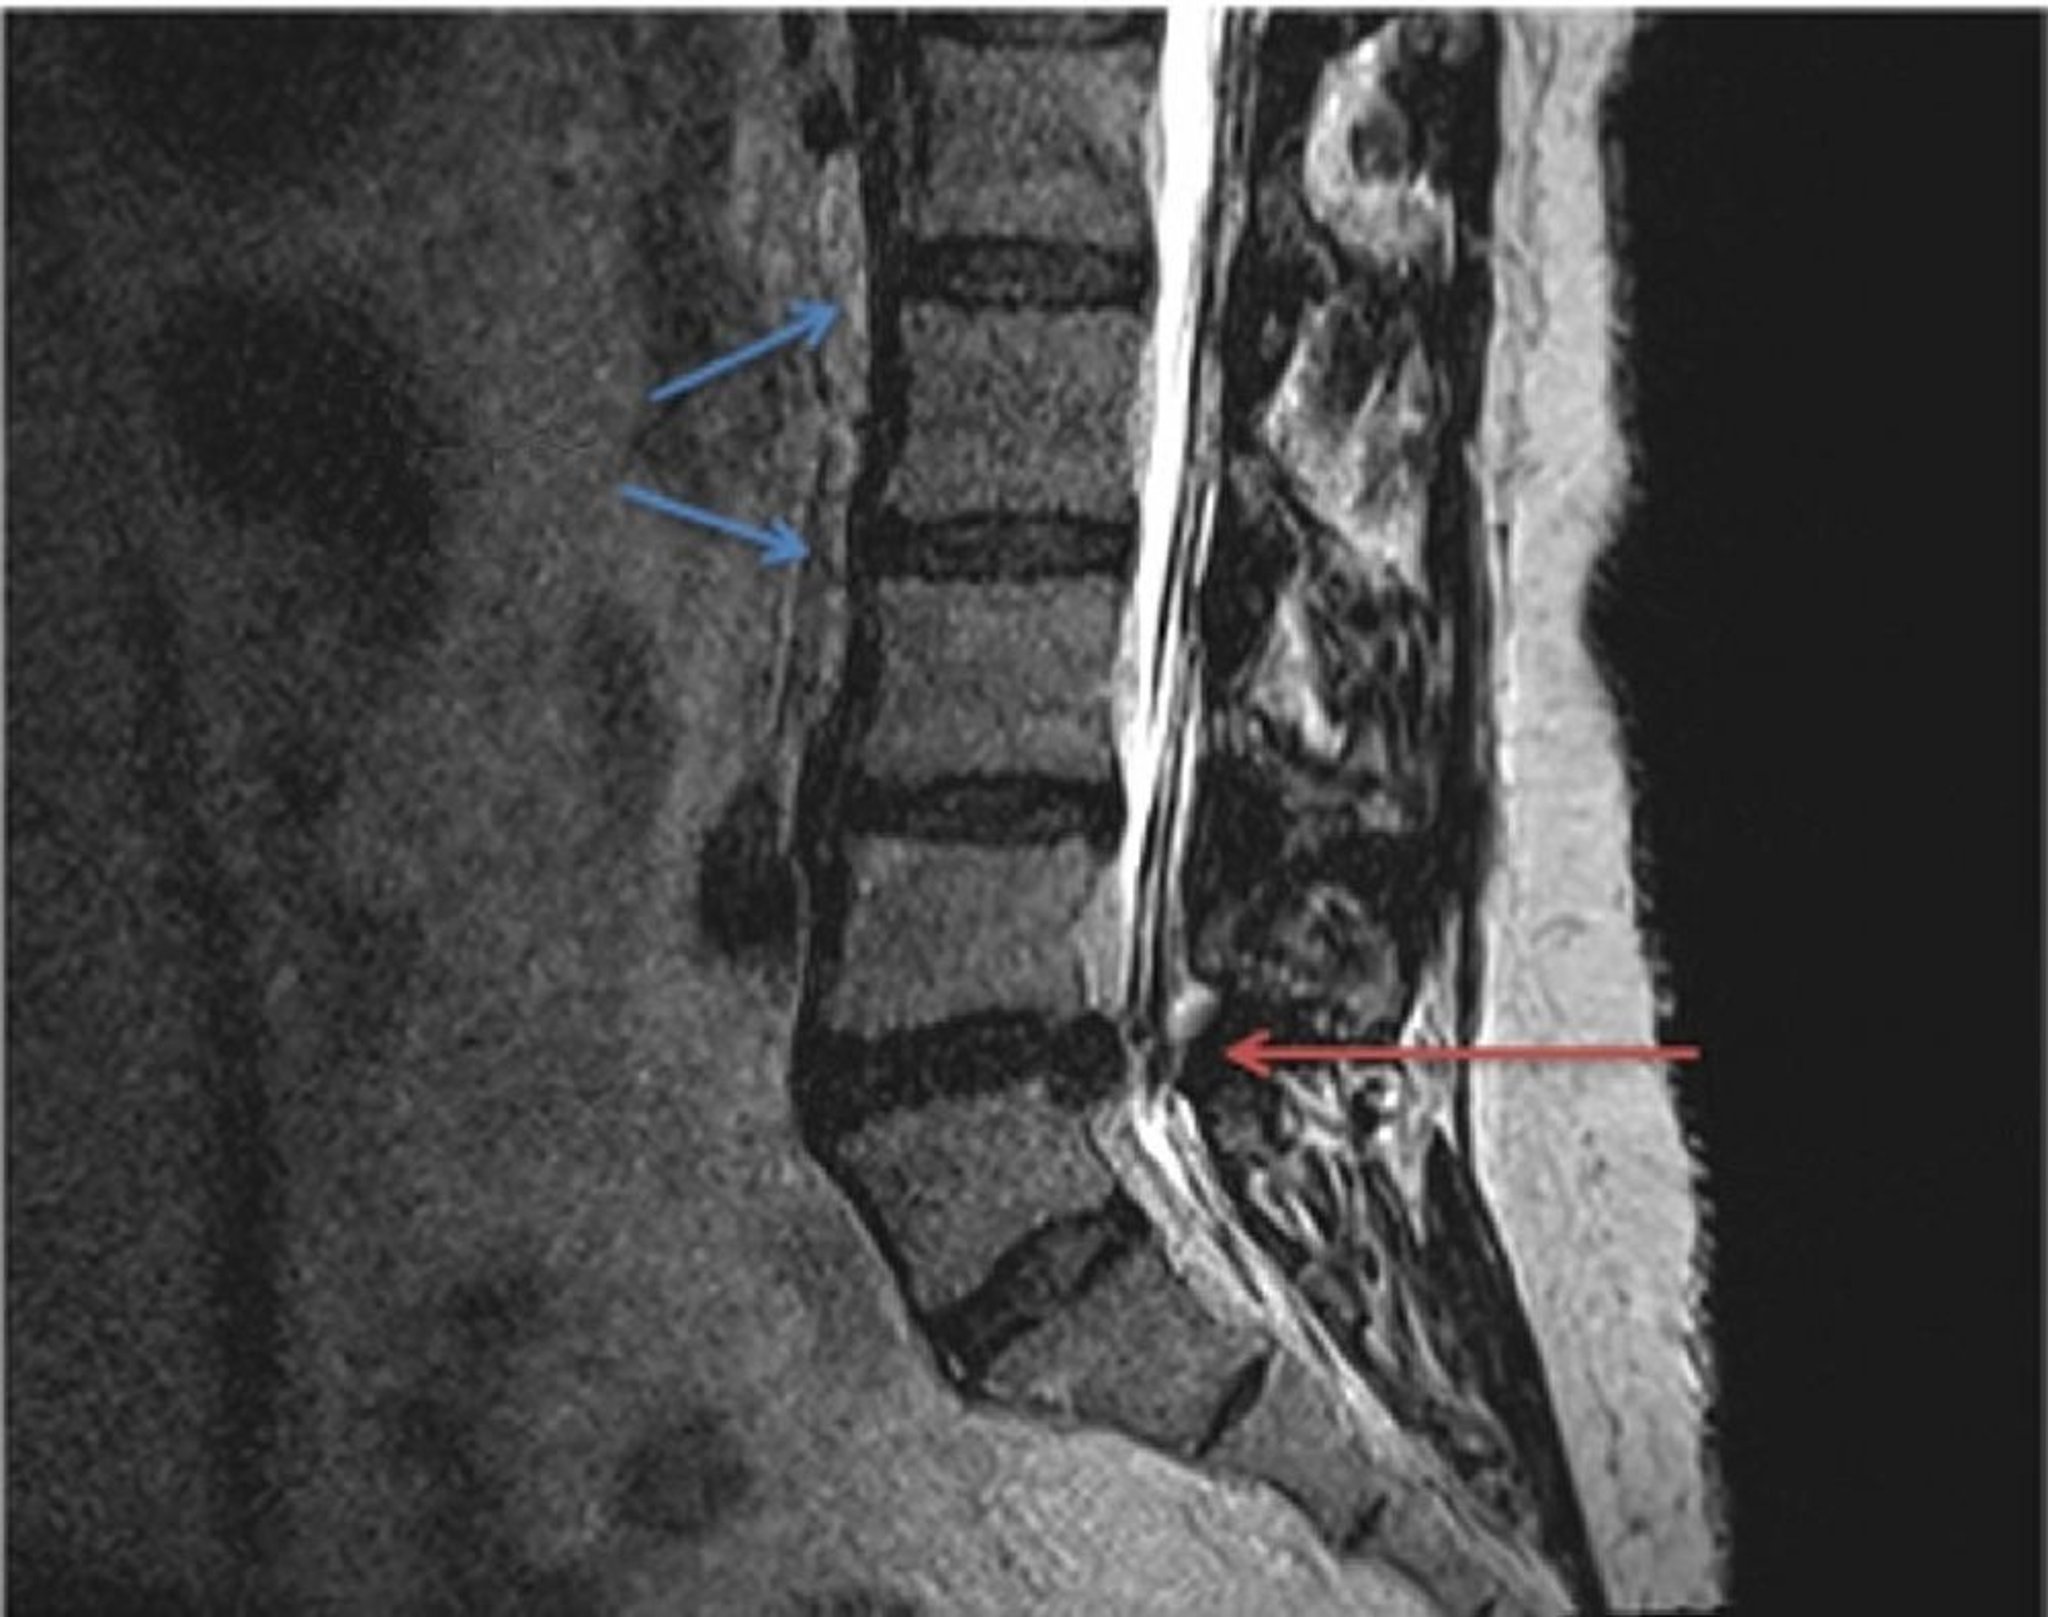

Грыжа межпозвоночного диска (МРТ-скан)

Сравнение анатомии нормальных (синие стрелки) и межпозвоночных дисков поясничного отдела с грыжами на МРТ-изображении в Т2-взвешенном режиме. Грыжа межпозвоночного диска, расположенного между L4 и L5 позвонками (красная стрелка), ущемляет спинномозговой нерв на протяжении от спинного мозга, что приводит к локализованному или иррадиирующему ощущению давления и боли.